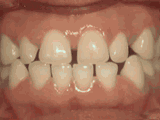

牙列拥挤,牙槽骨过窄,牙齿没有足够空间,只好前后左右高低上下乱长,经过矫正后的牙齿是这样的~